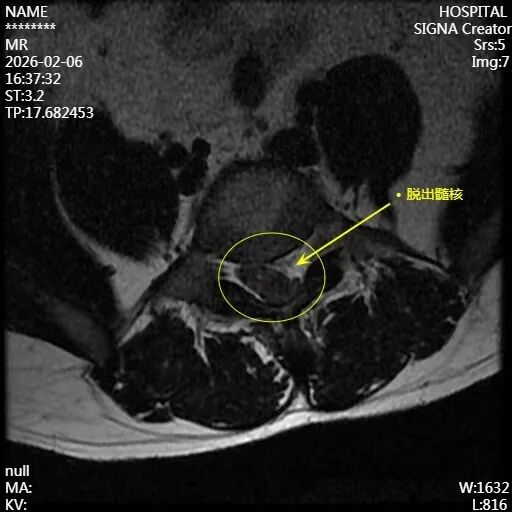

38岁的张先生(化名)被家人送来时,表情痛苦,双腿几乎无法挪动。他告诉医生,午休后突然腰像断了一样疼,随即发现脚麻了,上厕所也解不出小便。曾到当地专科医院诊治,被建议转省级医院治疗,后多方打听后来到淄博市第一医院脊柱外科就诊。

针对张先生的病情,陈越林、唐昱锋医师团队迅速制定手术方案,实施UBE内镜下腰椎后路减压+突出髓核摘除术。

手术核心目标:第一时间快速、彻底地清除突出的髓核组织,解除神经压迫,终止神经进一步损伤,同时稳定脊柱结构,为术后神经功能恢复创造条件。

当由于巨大的腰椎间盘突出(巨大髓核脱出)、外伤或肿瘤压迫到这一束神经时,就会引发马尾神经损伤(马尾综合征)。它的典型症状不一定是剧烈腰痛,而是一个严重的“预警信号”: